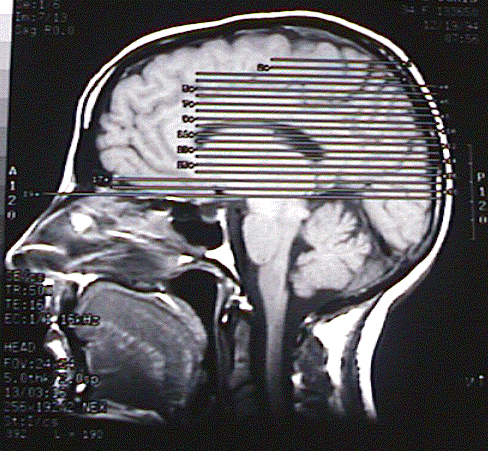

Click here for a QT movie of MRI scans of a brain tumor. (18 MB)

Here is a GIF animation of the same images.